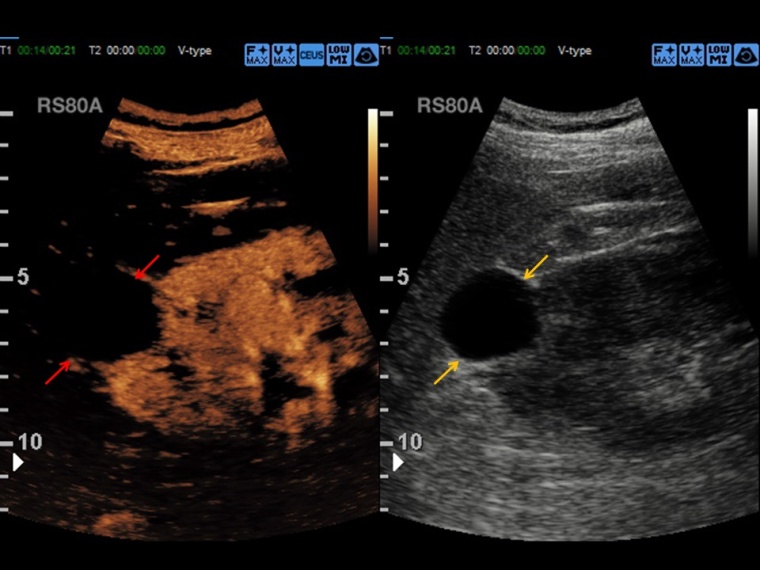

Der kontrastmittelverstärkte Ultraschall, CEUS (Contrast Enhanced Ultrasound) nutzt gasgefüllte Mikrobläschen als Kontrastverstärker zur Erstellung des Sonographiebildes.

Prof. Dr. Dirk-André Clevert: CEUS eignet sich hervorragend für die Beurteilung der Makro- und Mikrozirkulation von Organsystemen, die grundsätzlich für sonografische Fragestellungen untersuchbar sind. Dies umfasst diagnostische Fragestellungen im Bereich der Beurteilung von Läsionen und Raumforderungen von parenchymatösen Oberbauchorganen, aber auch die vaskuläre Diagnostik von Gefäßen, z. B. bei Patienten nach endovaskulärer Aortenreparatur. Ein Großteil der Diagnostik in unserer Abteilung behandelt die Abklärung von unklaren Leberraumforderungen oder komplexer Nierenzysten.

Clevert: CEUS ist eine schnelle, leicht durchzuführende und kosteneffektive Methode zur Diagnostik von abklärungsbedürftigen Befunden. Der Vorteil der Methode liegt in der schnellen Verfügbarkeit und der Dynamik der Untersuchungsmethode. Können in alternativen radiologischen Schnittbildgebungen beispielsweise nur einzelne Kontrastphasen akquiriert werden, so ist es mit dem CEUS möglich, die dynamische Perfusion von Gewebe oder von Gefäßen über mehrere Minuten zu beobachten, und so differenzierte Aussagen zu treffen. Ein weiterer großer Vorteil der Methode besteht darin, dass das verwendete Kontrastmittel unabhängig von der Nieren- und Schilddrüsenfunktion verwendet werden kann und somit der CEUS auch bei Patienten mit Niereninsuffizienz bzw. mit hyperthyreoter Stoffwechsellage zum Einsatz kommen kann.

Clevert: Eine großangelegte deutsche prospektiv-randomisierte Multicenter-Studie hat dies in der Vergangenheit in der Charakterisierung von Leberläsionen untersucht. Dabei konnte gezeigt werden, dass der CEUS eine Sensitivität von über 95 % und eine Spezifität von 83 % in der Charakterisierung von fokalen Leberläsionen zeigt und somit eine hohe diagnostische Aussagekraft besitzt.